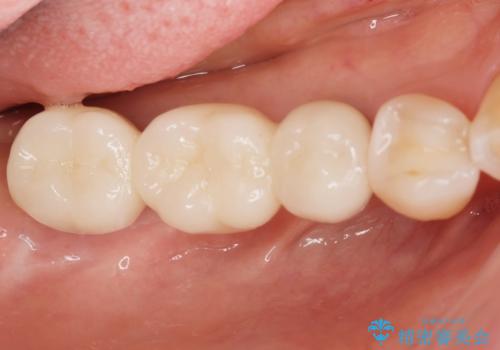

審美性が向上したとともに、またしっかりと噛めるようになったことで食事も楽しめるようになりました。

- 110万円(インプラント×2・チタンカスタムアバットメント×2・ジルコニアクラウン×3・仮歯×3)費用は治療当時の料金となります